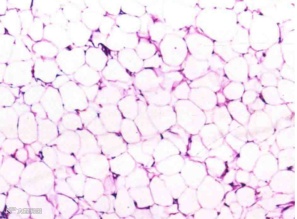

正常脂肪组织主要由大量群集的脂肪细胞构成

富贵包内纤维组织大量增生,相互包绕脂肪组织